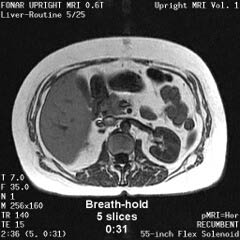

![]() |

The Liver, Kidney

and Small Intestine

|